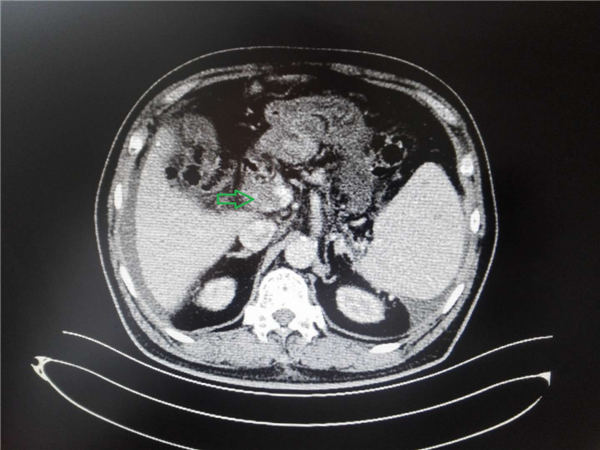

经CT检查显示:肝右后叶占位性病变,结合AFP增高,考虑原发性肝癌(红箭头所示),门静脉内大范围血栓形成(绿箭头所示)

经检查诊断后,考虑患者内镜下食管胃底静脉曲张治疗后复发,有再次出血风险,合并门脉内大范围血栓,不宜再次内镜下治疗,同时发现肝内占位性病变,考虑原发性肝癌。由于患者年老体弱,已经不适合外科手术治疗,但病情严重,迫切需要治疗,而食管胃底静脉曲张和原发性肝癌同时存在,治疗难度比较大。